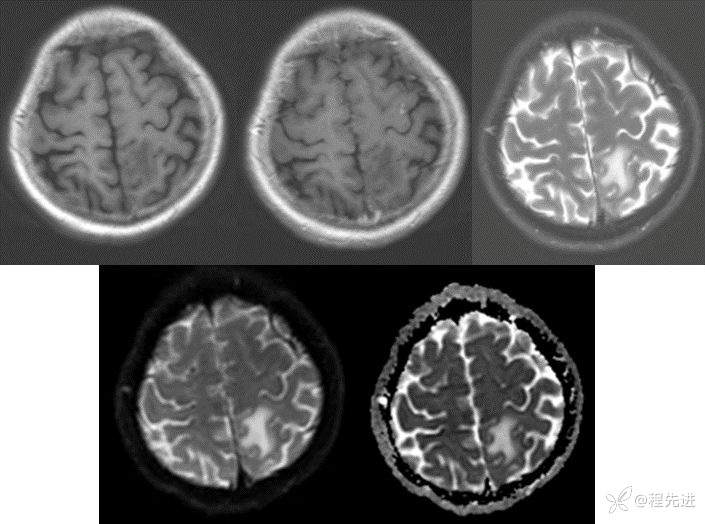

半年后:

img